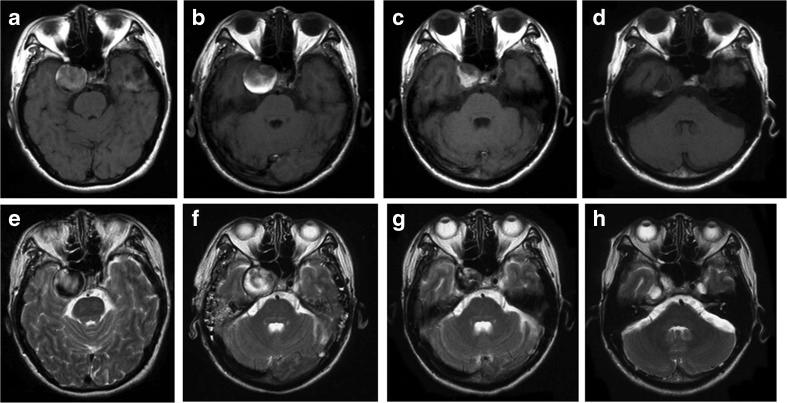

Aiming to define the optimal treatment of large and giant aneurysms (LGAs) in the anterior circulation, we present our surgical protocol and patient outcome. A series of 42 patients with intracavernous LGAs (n = 16), paraclinoid (C2) LGAs (n = 17), and peripheral (middle cerebral artery-MCA or anterior cerebral artery-ACA) LGAs (n = 9) were treated after bypass under motor evoked potential (MEP) monitoring. Preoperatively, three categories of ischemic tolerance during internal carotid artery (ICA) occlusion were defined on conventional angiography: optimal, suboptimal, and insufficient collaterals. Accordingly, three types of bypass: low flow (LFB), middle flow (MFB) and high flow (HFB) were applied for the cases with optimal, suboptimal, and insufficient collaterals, respectively. Outcome was evaluated by the Glasgow Outcome Scale (GOS). All patients had excellent GOS score except one, who suffered a major ischemic stroke immediately after surgery for a paraclinoid lesion. Forty-one patients were followed up for 87.1 ± 40.1 months (range 13-144 months). Intracavernous LGAs were all treated by proximal occlusion with bypass surgery. Of paraclinoid LGA patients, 15 patients had direct clipping under suction decompression and other 2 patients with recurrent aneurysms had ICA (C2) proximal clipping with HFB. MEP monitoring guided for temporary clipping time and clip repositioning, observing significant MEP changes for up to 6 min duration. Of 9 peripheral LGAs patients 7 MCA LGAs had reconstructive clipping (n = 4) or trapping (n = 3) with bypass including LFB in 3 cases, MFB in 1 and HFB in 1. Two ACA LGAs had clipping (n = 1) or trapping (n = 1) with A3-A3 bypass. The applied protocol provided excellent results in intracavernous, paraclinoid, and peripheral thrombosed LGAs of the anterior circulation.

为了确定前循环中大型和巨大动脉瘤(LGA)的最佳治疗方法,我们介绍了我们的手术方案和患者预后情况。42例患有海绵窦内LGA(n = 16)、床突旁(C2)LGA(n = 17)和周围型(大脑中动脉-MCA或大脑前动脉-ACA)LGA(n = 9)的患者在运动诱发电位(MEP)监测下进行搭桥手术后接受治疗。术前,在传统血管造影上定义了颈内动脉(ICA)闭塞期间的三类缺血耐受性:最佳、次优和侧支循环不足。相应地,分别对侧支循环最佳、次优和不足的病例应用了三种类型的搭桥:低流量(LFB)、中流量(MFB)和高流量(HFB)。通过格拉斯哥预后量表(GOS)评估预后。除1例因床突旁病变术后立即发生严重缺血性卒中外,所有患者的GOS评分均为优良。41例患者接受了87.1±40.1个月(范围13 - 144个月)的随访。海绵窦内LGA均通过近端闭塞并搭桥手术治疗。在床突旁LGA患者中,15例在吸引减压下进行直接夹闭,另外2例复发性动脉瘤患者通过HFB进行ICA(C2)近端夹闭。MEP监测指导临时夹闭时间和夹子重新定位,观察到持续长达6分钟的显著MEP变化。在9例周围型LGA患者中,7例MCA LGA患者进行了重建夹闭(n = 4)或包裹术(n = 3)并搭桥,其中3例采用LFB,1例采用MFB,1例采用HFB。2例ACA LGA患者采用A3 - A3搭桥进行夹闭(n = 1)或包裹术(n = 1)。所应用的方案在前循环的海绵窦内、床突旁和周围血栓形成的LGA中取得了优异的效果。